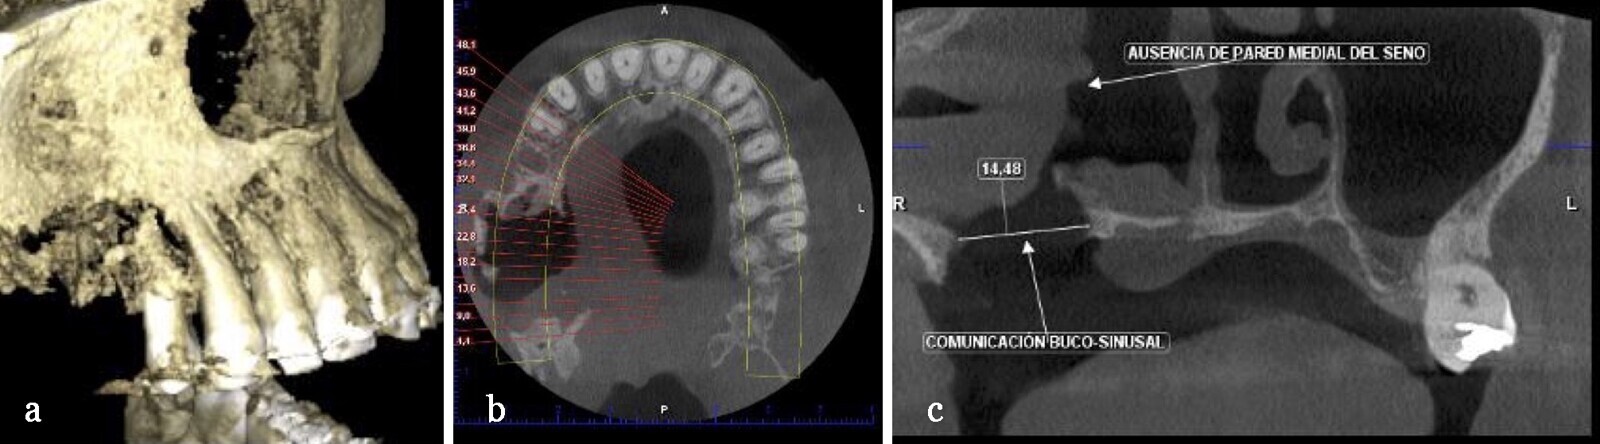

A los 4 meses postquirúrgicos, una tomografía axial computarizada de los senos paranasales del paciente consecuente con sus antecedentes sistémicos, encuentra sinusitis crónica maxiloetmoidal derecha, mucocele maxilar derecho, desviación septal e hipertrofia de cornetes inferiores, por lo cual se realizó una intervención quirúrgica consistente en etmoidomaxilectomia derecha, septoplastia y turbinoplastia por el servicio de otorrinolaringología.

Figura 3. Tomografía axial computarizada del maxilar superior del paciente (a), en la cual se observa un ocupamiento parcial del seno maxilar del lado derecho acompañada ausencia de la pared medial de seno maxilar compatible con comunicación oroantral (b), disminución de espacios medulares y engrosamiento de corticales óseas (c) correlacionadas con antecedentes quirúrgico infeccioso.